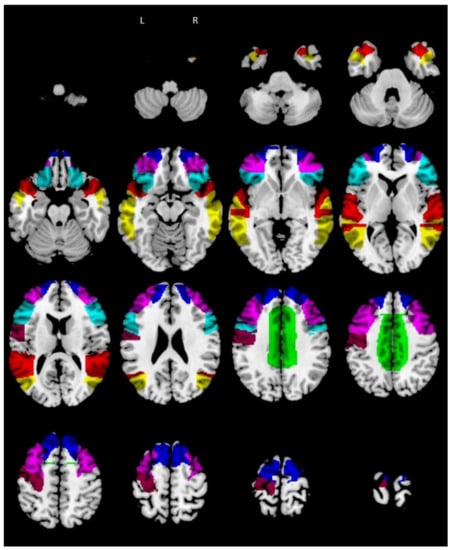

3.3. Hub and Spoke Definition